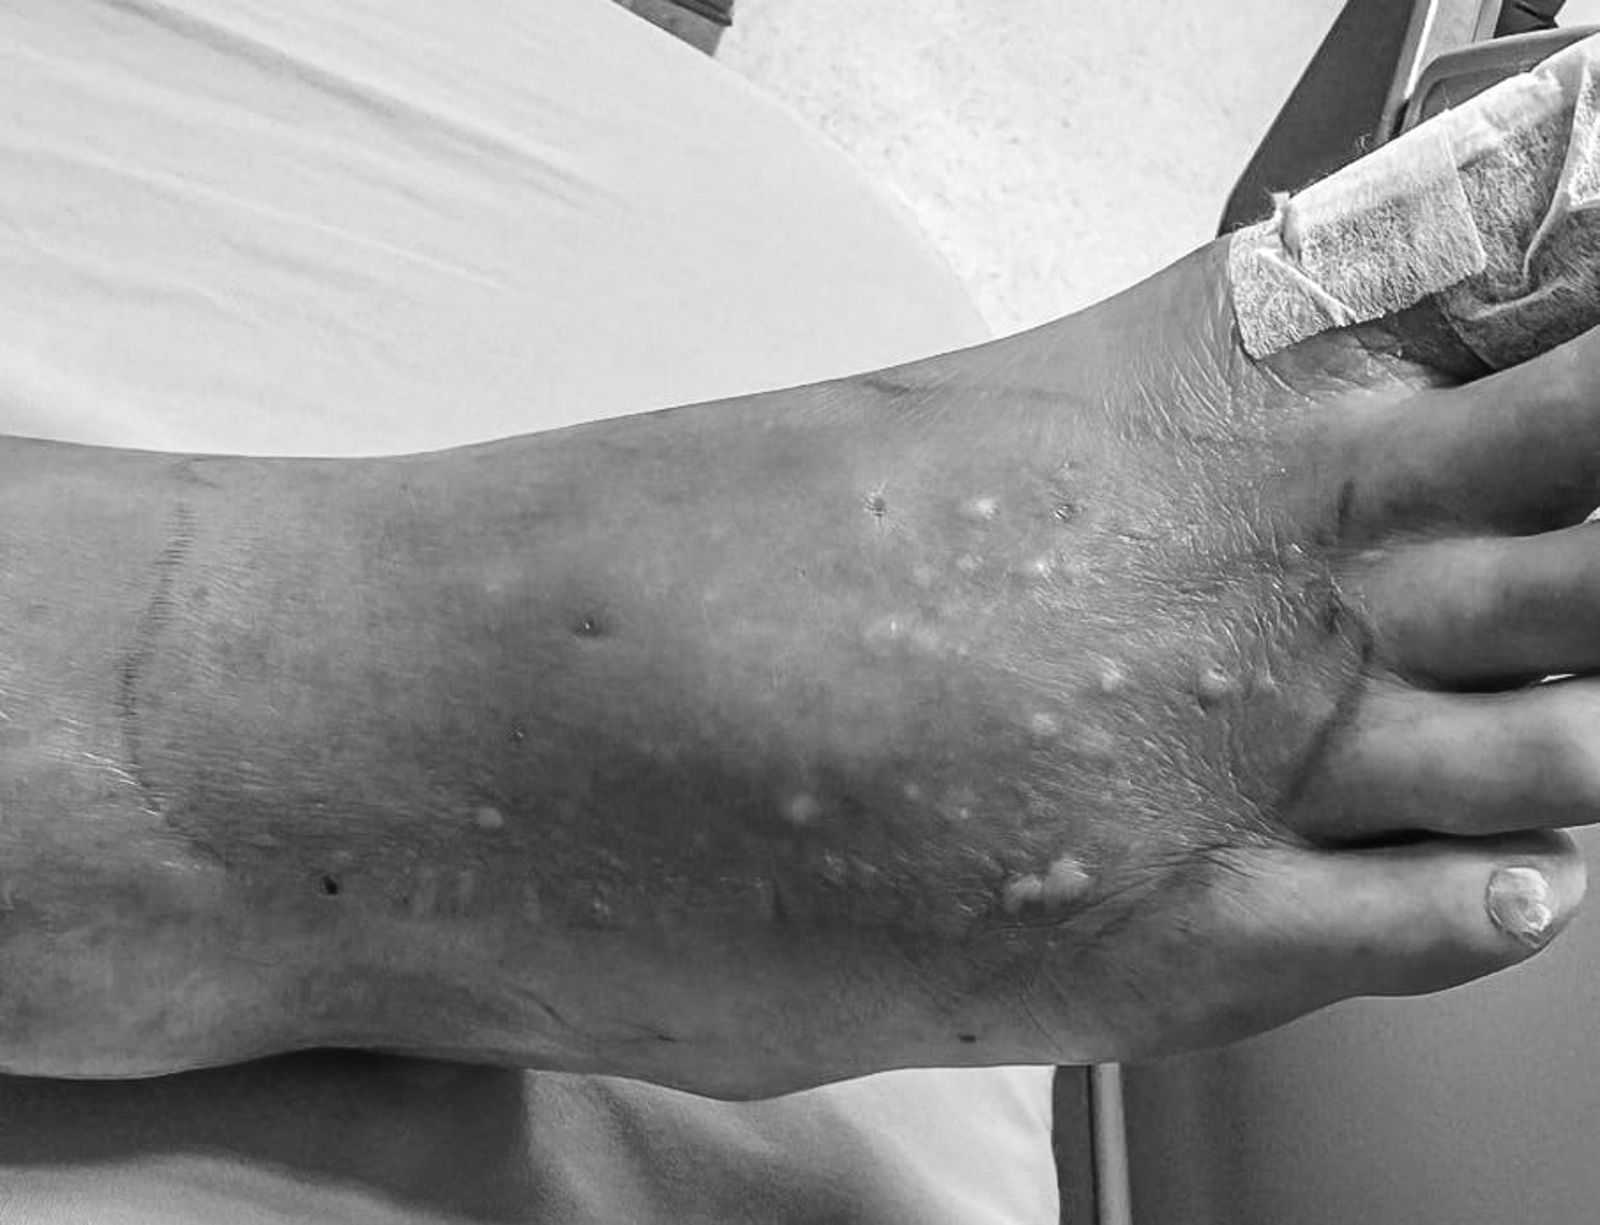

姜冠宇今於臉書po文,提到這個夏天蜂窩性組織炎的案例增加不少,不少比例還出現下肢或關節「化膿」、鼠蹊部腫大,而且不是僅限老人,有些案例還是有年輕人。「我本來覺得奇怪,一定要研究一下,後來發現其實不意外,因為『熱浪會促進炎症』」。